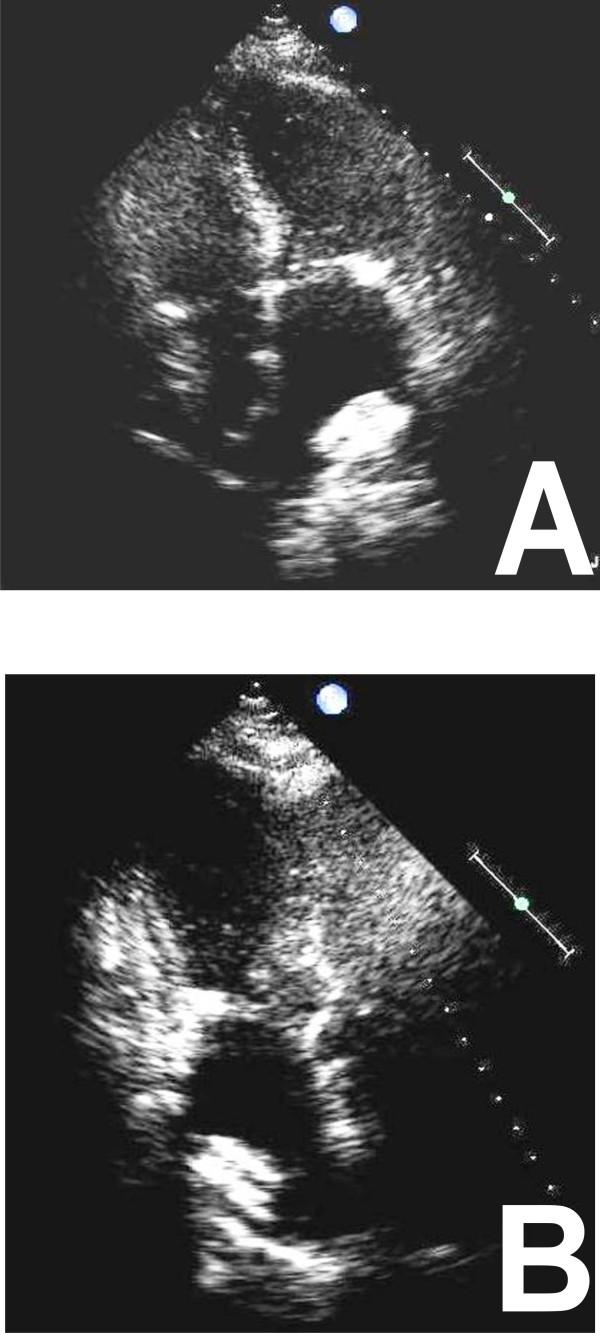

Aortic stenosis and mitral regurgitation, patent foramen ovale, interatrial septal defect, atrial fibrillation and perivalvular leak, are now amenable to percutaneous treatment. These percutaneous procedures require the use of Transthoracic (TTE), Transesophageal (TEE) and/or Intracardiac echocardiography (ICE). This paper provides an overview of the different percutaneous interventions, trying to provide a systematic and comprehensive approach for selection, guidance and follow-up of patients undergoing these procedures, illustrating the key role of 2D echocardiography.

主动脉瓣狭窄、二尖瓣反流、卵圆孔未闭、房间隔缺损、心房颤动及瓣周漏,目前均适合经皮治疗。这些经皮手术需要使用经胸超声心动图(TTE)、经食管超声心动图(TEE)和/或心内超声心动图(ICE)。本文概述了不同的经皮介入治疗,试图为接受这些手术的患者提供一种系统、全面的选择、指导及随访方法,并阐述二维超声心动图的关键作用。